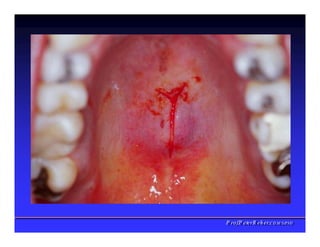

Face interna dos Lábios

✓Freios Labial

superior

✓Freio Labial

inferios

✓Bridas

Musculares